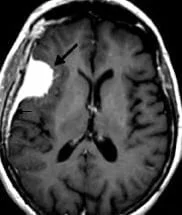

Un méningiome peut être diagnostiqué au scanner où il apparaît comme une masse ronde à la périphérie du cerveau, avec un épaississement de l’os au niveau de sa base d’insertion sur la méninge.

Il est plus fréquemment retrouvé sur une IRM sous forme d’une masse “blanche” après injection du produit de contraste intraveineux et entourée d’un œdème. Les méningiomes peuvent se rencontrer dans différentes localisations intra-crâniennes, plus ou moins facilement accessibles et qui conditionneront la technicité et les risques du geste qui vous sera proposé par votre chirurgien.

frontal droit